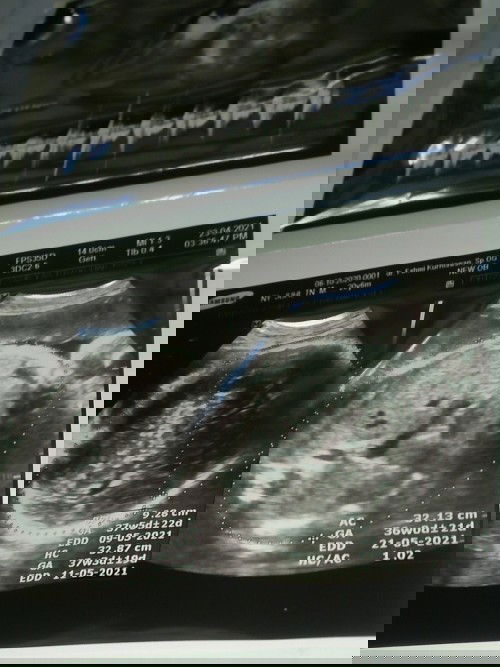

klo GA itu usia kehamilan, EDD perkiraan tanggal lahir, AC itu BB bayi

emang dokternya ga jelasin berapa berat janinnya bun? udah masuk minggu 36-37 soalnya itu, biasanya dokter jelasin beratnya udah cukup atau masih kurang.

itu keterangannya kaga lengkap bun usgnya. biasanya ada keterangan EFW satuannya gr